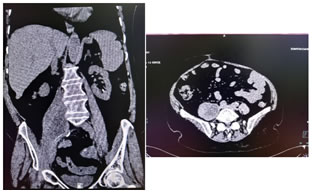

Investigations include complete blood count, differential count, C reactive protein, ESR, urine routine and culture, blood culture, renal and liver function tests, vaginal and endocervical swabs. Ultrasound is the first line investigation for radiological diagnosis, however the diagnosis is often missed because of lack of clinical suspicion. Even with clinical suspicion, it is diagnostic in only 60% of cases 6. Sonography is also essential to rule out the evidence of any retained products of conception. Simple abdomen radiography can demonstrate blurring of the psoas muscle region, and air enhancing duodenal or renal contour, although its diagnostic value for psoas abscess is restricted . The sacroiliac joint, the lumbar spine, and intervertebral disks should be carefully examined. If a lesion is too small to reveal soft tissue gas, spinal destruction, mass effects or unusual iliopsoas, plain films would only reveal negative findings 7. CT is the most accurate investigation for diagnosis of iliopsoas abscess with reported sensitivity of 100% and specificity of 77% 8. Few studies state that the magnetic resonance imaging (MRI) can differentiate soft tissues more accurately, producing a clear view of the abscess wall and its surrounding structures without the use of a radiocontrast agent, thus, making the MRI a better choice than the CT scan 9. On CT scans, an abscess may manifest as enlargement of the iliopsoas muscle by a low-attenuation lesion [FIG 1, FIG 2]. The lesion typically displays rim enhancement after the intravenous administration of contrast material . Abscesses appear as areas of low signal intensity at nonenhanced T1-weighted MR imaging and as areas of high signal intensity at nonenhanced T2-weighted MR imaging [FIG 3]10. Secondary findings include obliteration of the surrounding fascial planes, bone destruction, and gas bubbles. CT is more sensitive than MR imaging for demonstrating gas bubbles.11

Figure 1                                                                                     Figure 2

Figure 1: Coronal and Axial CT images showing normal appearance of bilateral psoas muscles which show uniform attenuation and well defined margins; Figure 2: Non contrast axial and coronal CT images showing right psoas abscess; Figure 3: T2w axial and post contrast T1FS axial and coronal images showing right psoas abscess